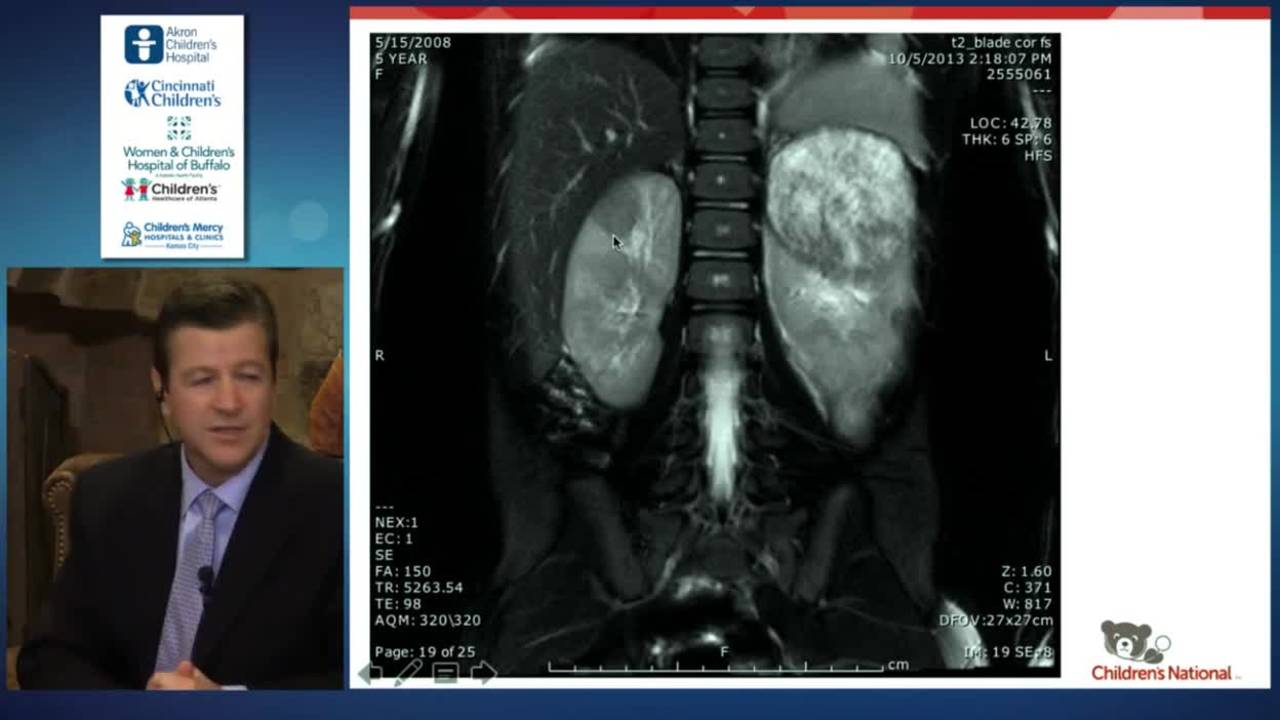

This video appears in a new pediatric surgery textbook, Clinical Pediatric Surgery: A Case-Based Interactive Approach," by Dr. Sherif Emil. The book is an innovative educational resource that focuses on judgment and decision-making in pediatric surgery. If you’d like to learn more, watch this short video or read this short article.